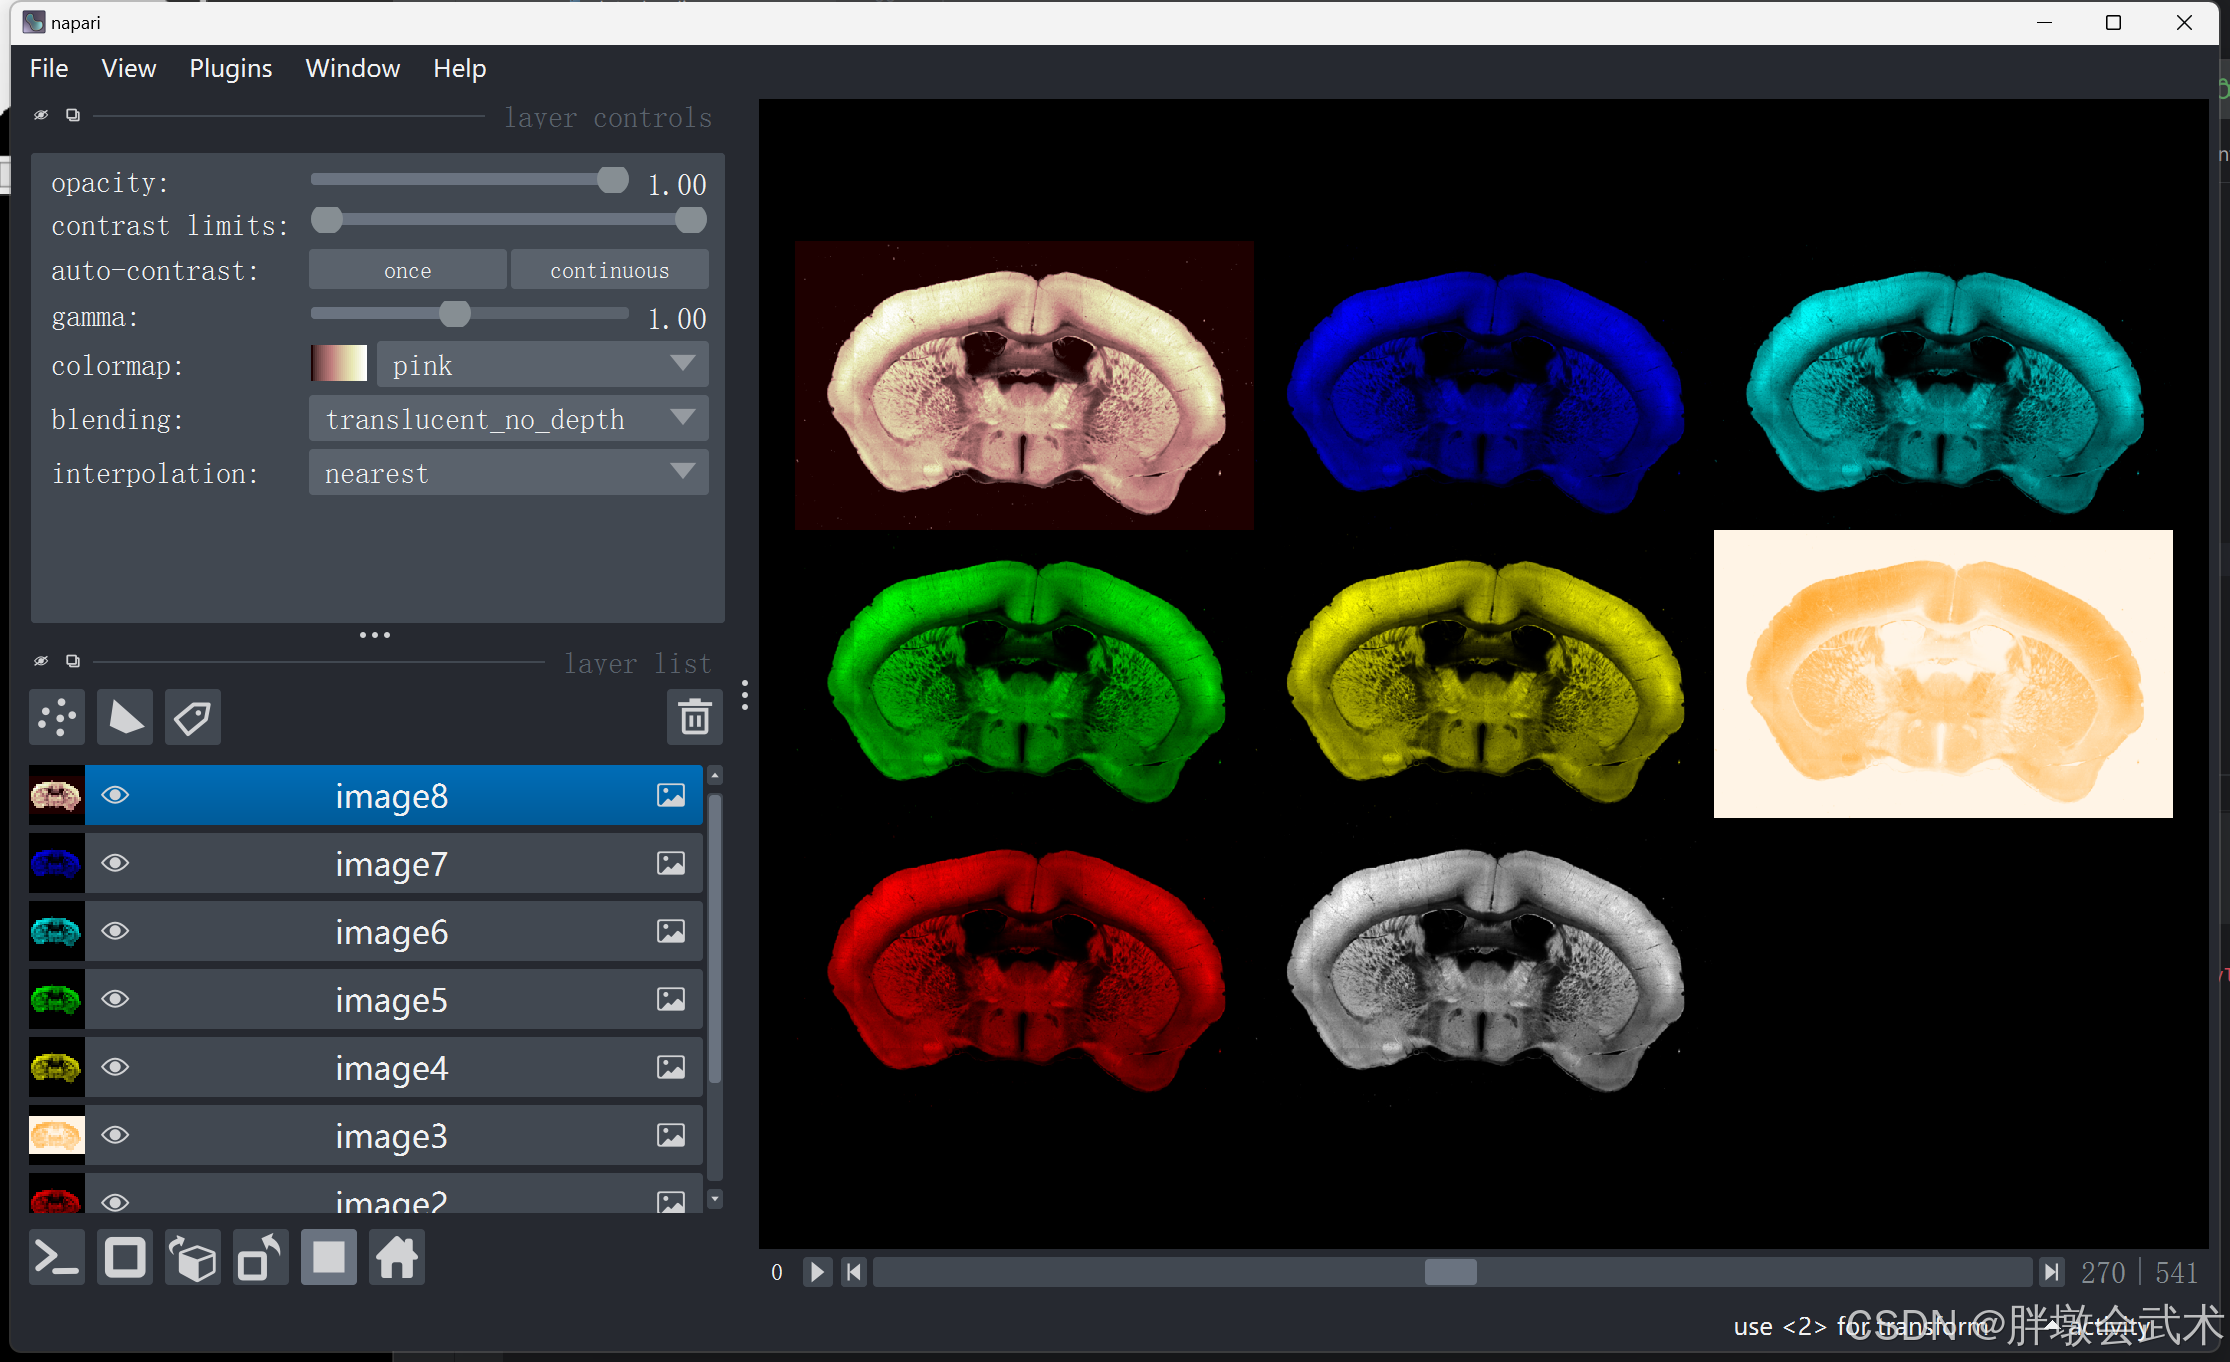

3.2.3、(自动)启动网格视图模式(Toggle grid mode)

import napari

import tifffile

if __name__ == '__main__':

image_path = r'F:\py\YH220.tif'

image = tifffile.imread(image_path)

viewer = napari.Viewer() # 创建 napari 视图

viewer.add_image(image, name='image1')

viewer.add_image(image, name='image2', colormap='red') # 红

viewer.add_image(image, name='image3', colormap='orange') # 橙

viewer.add_image(image, name='image4', colormap='yellow') # 黄

viewer.add_image(image, name='image5', colormap='green') # 绿

viewer.add_image(image, name='image6', colormap='cyan') # 青

viewer.add_image(image, name='image7', colormap='blue') # 蓝

viewer.add_image(image, name='image8', colormap='pink') # 粉(不支持紫色)

viewer.grid.enabled = True # 启动网格视图模式

viewer.grid.shape = (3, 3) # 设置网格的行和列数

napari.run() # 显示 napari 视图